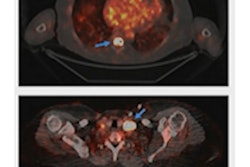

The ACS also noted that there have been rapid reductions in lung cancer mortality, noting that non-small cell lung cancer (NSCLC) is a common condition that typically has a poor prognosis. Two-year relative survival for NSCLC has increased from 34% for patients diagnosed from 2009 through 2010 to 42% for those diagnosed between 2015 and 2016.